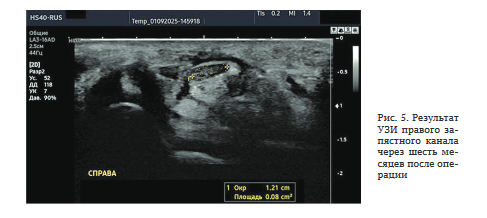

Результат УЗИ: ППС срединного нерва в запястном канале — 8 мм2 (рис. 5).

Ультразвуковое исследование проводили на обеих верхних конечностях с помощью аппарата Samsung Medison HS 40, используя линейный датчик с частотой 3-16 МГц. В ходе сканирования идентифицировали срединный нерв, его размеры, структуру, места сдавления нерва на запястье и в верхней трети предплечья, расположение мышц тенара в зоне запястного канала, состояние окружающих тканей, мышц и сухожилий.